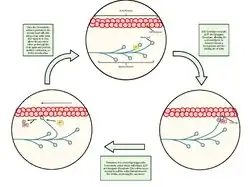

Las "células satélite" son una población heterogénea, formada por células madre y células progenitoras residentes, localizadas entre la lámina externa y el sarcolema de cada fibra muscular. Representan entre el 1-4% de todos los núcleos asociados con las fibras musculares adultas.

Las "células satélite" son responsables de: el crecimiento, la reparación y la regeneración de la fibra muscular.[13]

Las células madre satélite habitualmente inactivas en la fase G0, se multiplican en respuesta a estímulos fisiológicos como: el ejercicio, las lesiones y el estrés.[14]

Después del daño de la miofibra, las células satélite, se activan para ingresar al ciclo celular y proliferar.[15]

Rotura fibrilar y Reparación

En las lesiones musculares y las enfermedades musculares, la capacidad de regeneración es esencial para recuperar la función. En respuesta a la lesión muscular, las células satélite (SC) se activan para iniciar la diferenciación miogénica, acompañada de una expresión regulada al alza de miogenina (MYOG) y el factor4 regulador específico del músculo. El programa de diferenciación luego se completa con la activación de proteínas musculares específicas como miosina (MYHC) en los mioblastos que se fusionan para regenerar las miofibras.[16]